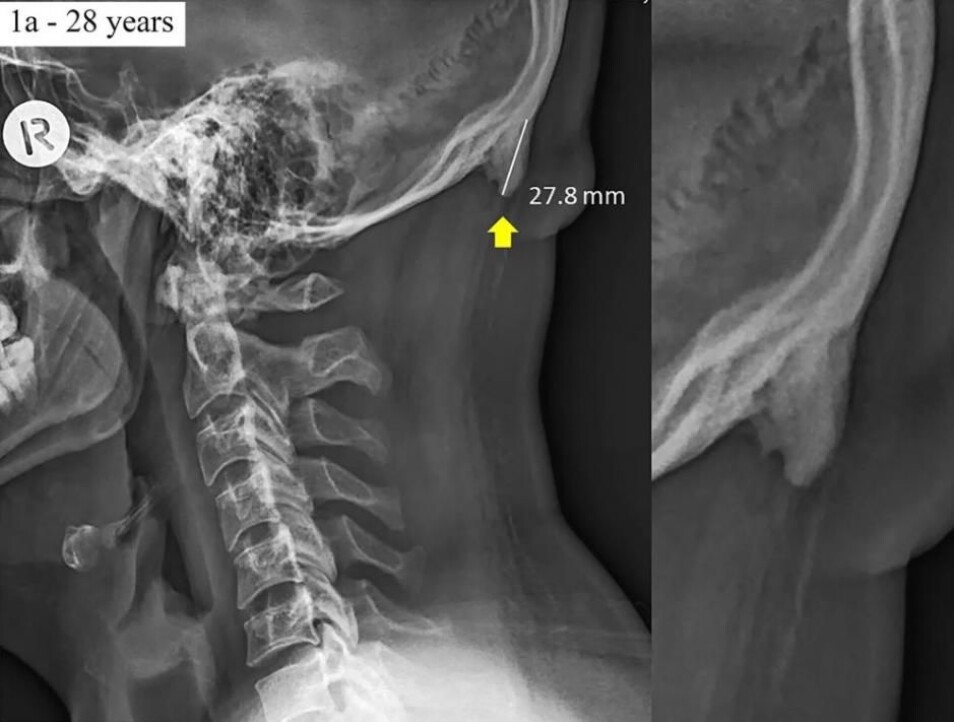

Et røntgenbilde av en 28 år gammel mann, der du kan se «hornet». (Foto: Shahar and Sayers/Scientific Reports)

Forskerne begynte på forskningsprosjektet for tre år siden, da de så på røntgenbilder av kraniet på 218 personer i alderen 18–30 år. I studien ble knokkelveksten observert hos 41 prosent av de unge og var mest utbredt blant menn.

Forskerne altså protuberantia occipitalis externa bakgrunn av røntgenbildene og fant en knokkelvekst hos 33 prosent av gruppen. I noen tilfeller helt opptil to centimeter.